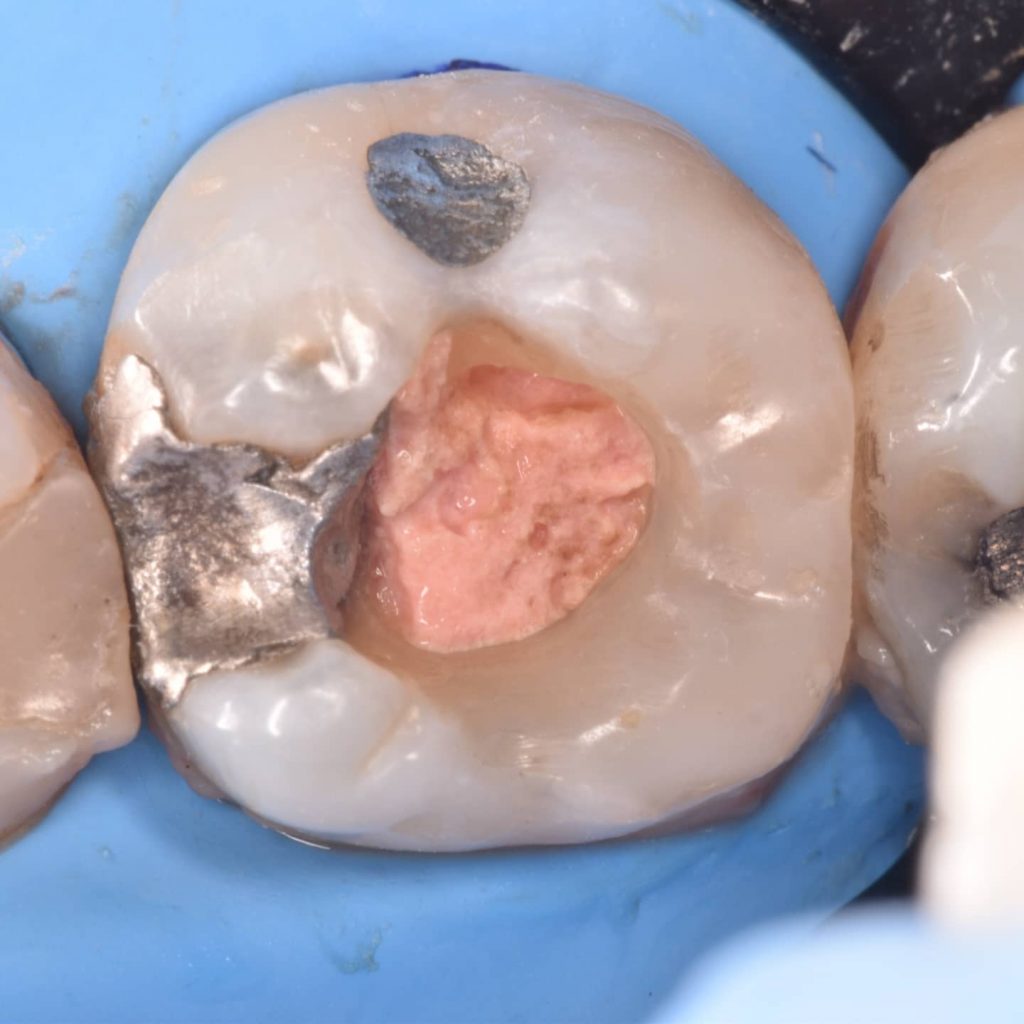

After 6 month of endo treatment the pateint come to complete the final filling as you see the amalgam mesaily should removed

Amalgam removal

Ever x posterior for more support to the filling and for dentin replacement